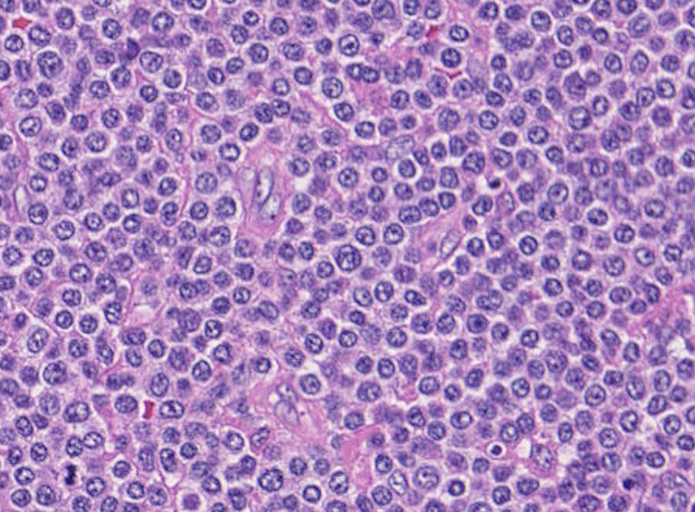

腫瘍細胞は腸管全層に密に浸潤している。粘膜表面は上皮が消失しびらんを形成。(Fig.1), 高倍率では中型, medium sized(組織球の核とほぼ同じサイズ)の類円形核をもつ比較的淡明な細胞質の異型リンパ球様細胞が密にmonotonousな増殖を示している。(Fig.2,3)

粘膜固有層には腫瘍細胞が充満し腺窩基底膜側より陰窩内に進入してIntraepithelial lymphocyte(IEL)の上皮浸潤を模倣する特徴的な蚕食像を示している。(Fig.4)

Pathological Diagnosis: Enteropathy-associated T cell lymphoma, monomorphic type

CD3ε+, CD8+, CD56-, TIA-1+, CD4-, CD5-, CD10-, CD20-, CD30-, UCHL-1-

- monotonous small round cell subtypeでは, CD8+, CD56+